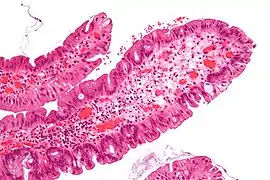

Micrograph of a Peutz–Jeghers colonic polyp – a type of hamartomatous polyp. H&E stain.